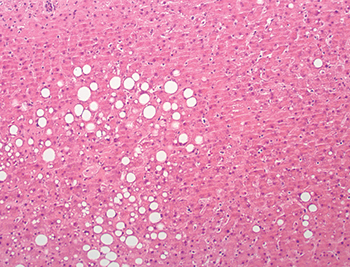

Hepatic steatosis is assessed as the percentage of the biopsy involved by macrovesicular or “large-droplet” steatosis. In macrovesicular steatosis, one or a few large fat droplets displace the nucleus to the edge of the hepatocyte (Fig. 3.1.4). Frozen section may be used to assess potential graft organs for steatosis because steatosis cannot be reliably assessed by gross evaluation, and moderate or severe steatosis has been associated with increased risk of poor or delayed graft function in some series. There is no uniformly acceptable amount of steatosis, and reported graft and patient outcomes for steatotic livers vary widely. Grafts with less than 30% steatosis are usually considered suitable for transplantation (Fig. 3.1.5), whereas those with greater than 30% (Fig. 3.1.6) or even greater than 60% (Fig. 3.1.7) are less desirable but have been used successfully in some circumstances. Special stains for fat (oil red O) may be used in steatosis assessment but are not required. “Small-droplet” steatosis refers to a single or few small lipid droplets that do not displace the nucleus (Fig. 3.1.8). This finding alone does not adversely impact graft function. Pure microvesicular steatosis is a rare finding that manifests as multiple tiny lipid droplets that surround the nucleus and impart a foamy or vesicular appearance to the hepatocyte cytoplasm (Fig. 3.1.9). Pure microvesicular steatosis likely represents an agonal or ischemic change that does not impact graft function.